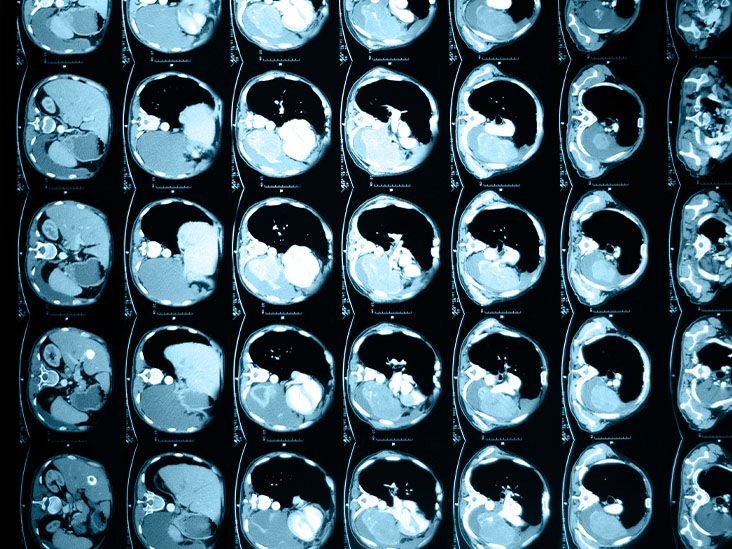

א ניסוי קליני מ Keck Medicine מ-USC שואפת לספק פתרון כירורגי לחולים עם סוג של סרטן לבלב מתקדם שנחשב בעבר